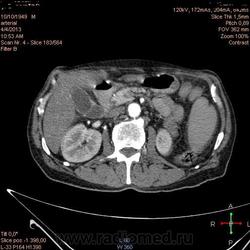

Здравствуйте, коллеги.Помогите разобраться.Пациент 1949 г беспокоять боли в животе , отсутствие аппетита, похудание .За неделю пожелтел, ослаблен.Нужно исключит кацер головки подж.железы.Анализы сегодня сдал еще не готовы.УЗИ зак увеличение л\узлов у ворот печени.Образов головки подж.железы ?На КТ жировой гепатоз.вроде головка подж железы не увеличены.

Мне надо исключить или поставить образование головки подж.железы.Хирурги ждут заключение, хотять оперировать.

А про билиарную гипертензию на УЗИ и КТ ничего не говорится?

Даже если вы пропустили малый рак панкреас, пациент умер не из-за него - желтуха не механическая, а, вероятней, паренхиматозная.